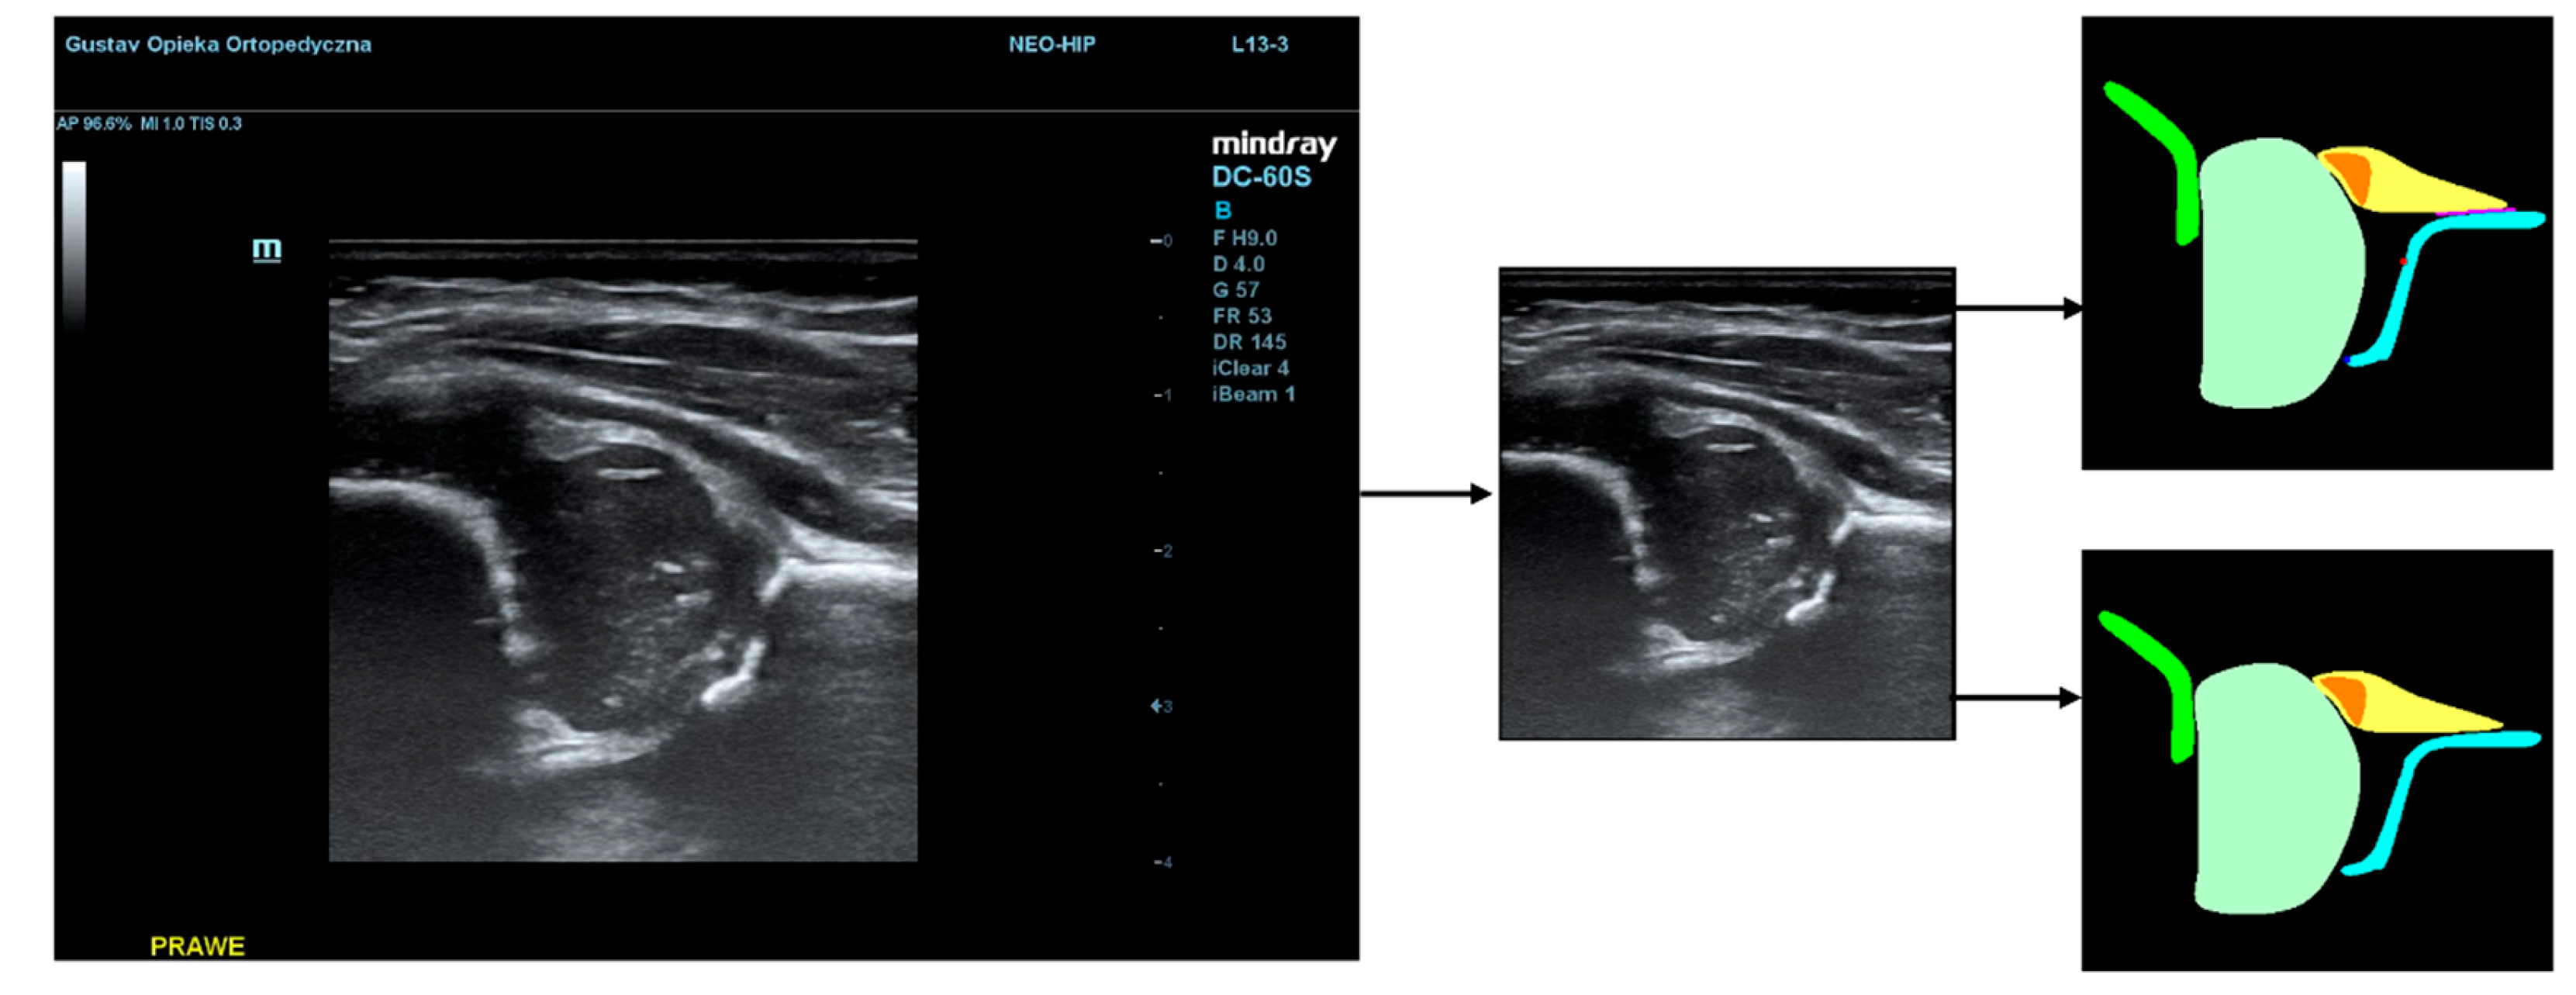

To illustrate the performance of the segmentation model, a comparison is presented between the labels obtained by the segmentation model and the ground truth labels. Two models were analyzed: Model-8 (generating segments for 8 classes) and Model-5 (generating segments for 5 classes). Both the cases with the highest quality model labels and the cases where the model labels were less accurate are presented. Figure 3 shows one of the best cases, in which Model-5 and Model-8 accurately labeled the classes relative to the doctor's labels. The worst-case scenario was also analyzed, in which the prediction results differ significantly from the ground truth labels (Figure 4).

Figure 3. High quality model labels (upper - Model-8) and (lower - Model-5). Annotated mask on the left, model mask on the right.